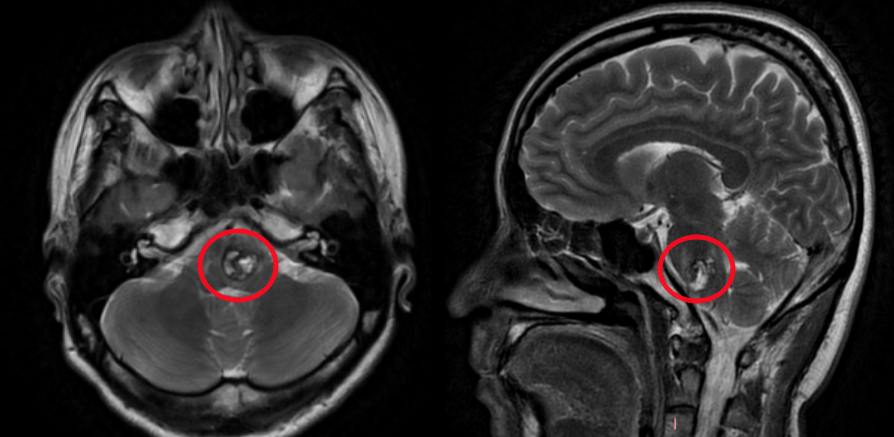

2023年9月琳琳核磁影像